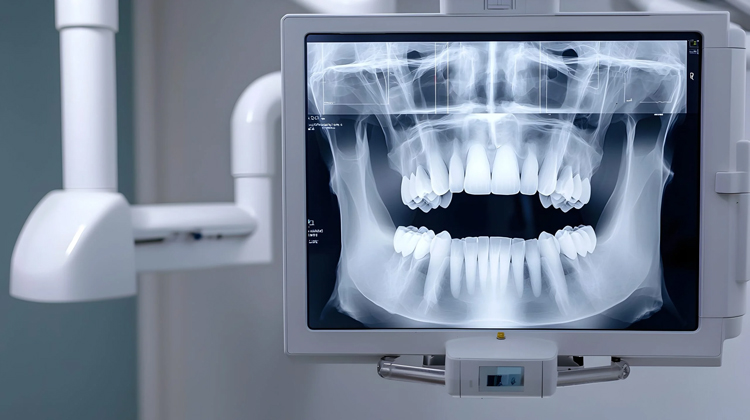

3D Tomografi Nedir?

3D tomografi, diş hekimliğinde kullanılan en gelişmiş görüntüleme yöntemlerinden biridir. Geleneksel röntgenlerden farklı olarak, diş, çene ve yüz yapısını üç boyutlu şekilde gösterir. Bu sayede en ince ayrıntılar dahi görülebilir ve tedavi planlamasında hatasız sonuçlar elde edilir. Özellikle implant cerrahisi, çene eklem sorunları ve gömülü dişlerin konumlandırılması gibi durumlarda büyük avantaj sağlar.